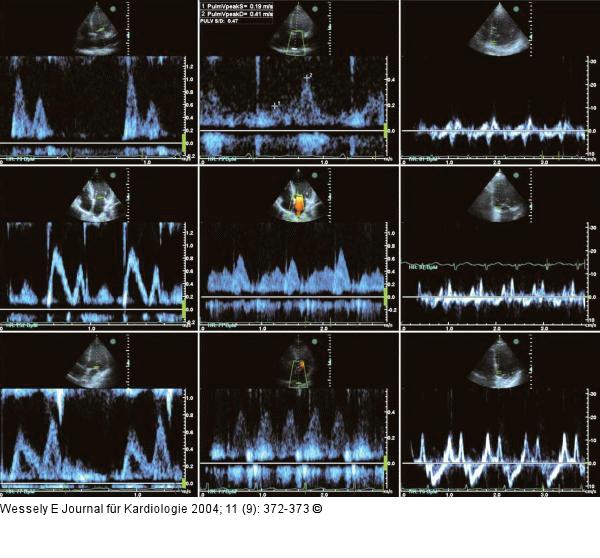

Abbildung 1: Diastolische Compliancestörung Linke Spalte oben, Mitte, unten: apikaler Vierkammerblick, PW-Dopplersignal des diastolischen Einstromes im Bereich der Segelspitzen der Mitralklappe. Mittlere Spalte oben, Mitte, unten: apikaler Vierkammerblick, PW-Dopplersignal im Bereich der Einmündung der rechten oberen Lungenvene. Rechte Spalte oben, Mitte, unten: apikaler Vierkammerblick, Gewebedopplersignal in Höhe der Herzbasis, septumnaher Mitralring. |